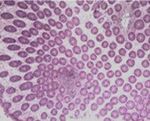

Figure 4. Microscopic image of the expelled mass

Figure 2. Microscopic image of the biopsy from colo-

reveals mature and natural adipocytes (H&E stain,

noscopy shows colonic hyperplastic polyp with ero-

×100).

sion (H&E stain, ×100).